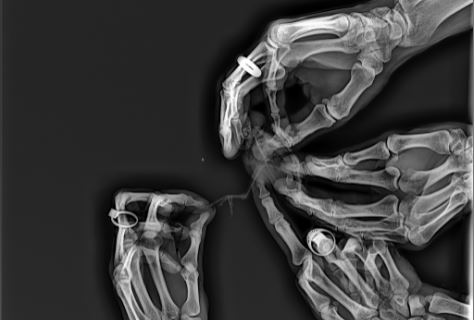

Snad každý z nás byl u lékaře, ať už kvůli čemukoli. Ne každý tam však byl kvůli zlomenině, a tak ne každý zažil rentgen. Samozřejmě je všeobecně známo, co že to ten rentgen je. A my vám dnes ukážeme 10+ rentgenových snímků, které nám ledacos prozradí.

4. Kočičí packa.

5. Vrozená vada prstů.